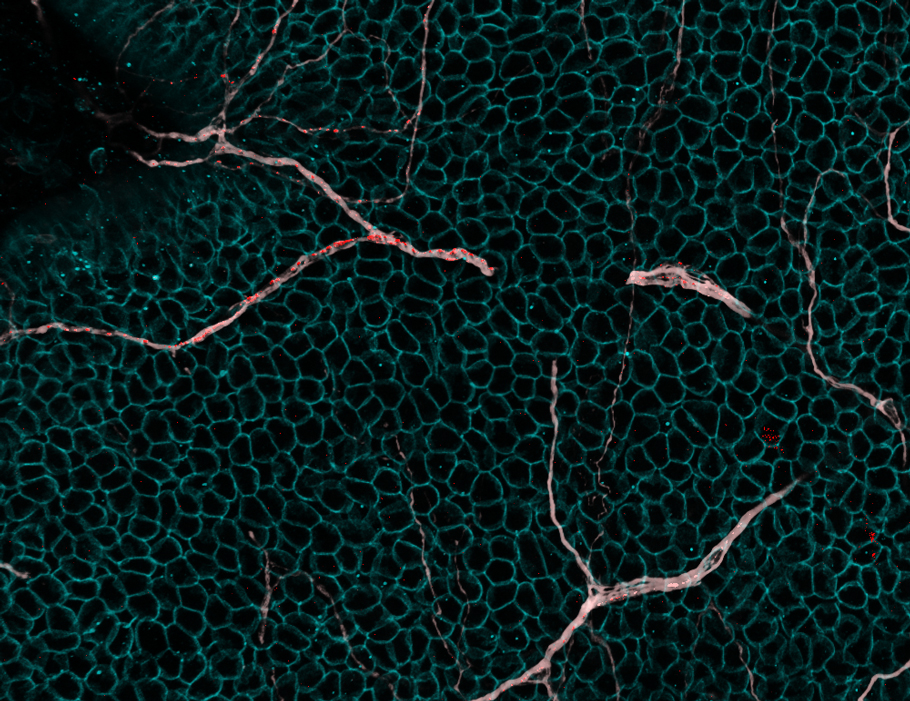

Happy #3DThursday! I'm quantifying some microglia morphology and trying to figure out why sometimes these cells start eliminating neuronal synapsesπ§ Markers: IBA1 for microglia, PSD95 for synaptic protein. Z-stack image acquired with ZEISS Microscopy, analysis with Imaris 3D/4D Imaging